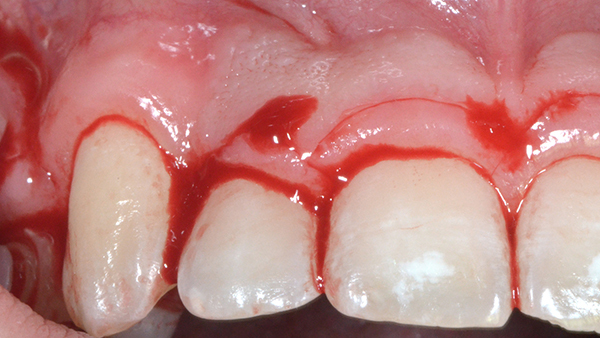

Diş tacının cərrahi uzadılması müxtəlif kliniki hallarda müxtəlif məqsədlərlə tətbiq edilən cərrahi müalicə prosedurudur. Bu metod estetik stomatologiyada “Gummy smile” (diş əti gülüşü) olaraq adlandırılan durumun ortadan qaldırılması məqsədilə geniş tətbiq olunur. Bu zaman kliniki hala bağlı olaraq bəzən yalnız diş əti, bəzən isə həm diş əti həm də sümükdən müəyyən miqdarda rezeksiya edilməklə (kəsilməklə) diş və diş ətinin estetik cəhətdən ideal görünüşü əldə olunur.

Bundan başqa, travma, ciddi karioz zədələnmə, normadan artıq preparasiya (diş yonulması) və s. nəticəsində diş tacının böyük ölçüdə dağılması zamanı bu dişlərin üzərinə qapaq, körpü konstruksiyalarının hazırlanması və ya bu dişlərin çıxan diş konstruksiyaları üçün (məsələn: teleskopprotezlər) fiksasiya elementi olaraq hazırlanması mümkün olmur. Buna səbəb diş toxumasının normadan artıq dağılmasıdır. Bu zaman tətbiq edilən metodlardan ən başlıcası diş tacının cərrahi uzadılmasıdır. Bu metodun tətbiqi ilə sümük müəyyən miqdarda uzaqlaşdırılaraq dişin tac hissesi uzadılmış olur. Nəticədə protetik olaraq yararsız diş yararlı duruma gətirilir.